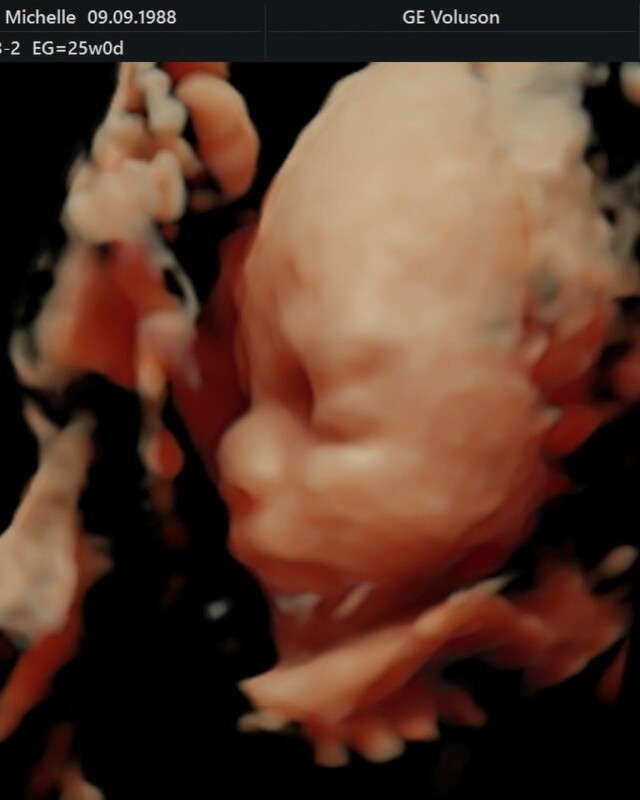

Sin embargo, dentro de las diversas fotografías familiares, la que más sobresalió fue la ecografía tridimensional de la carita del bebé que llevará por nombre Milo, la cual recibió un sinfín de comentarios de cariño.